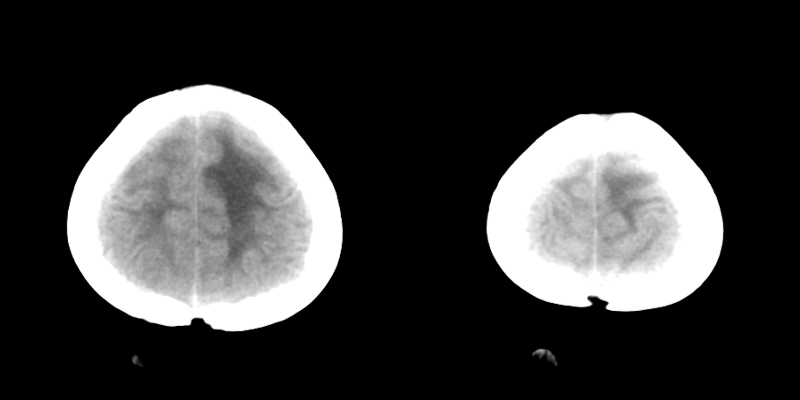

低位梗阻性脑积水。可怜!做手术吧!

我认为是交通性脑积水,幕上幕下脑室都扩张,建议mr检查!

考虑梗阻性脑脑积水。

低位梗阻性脑积水。